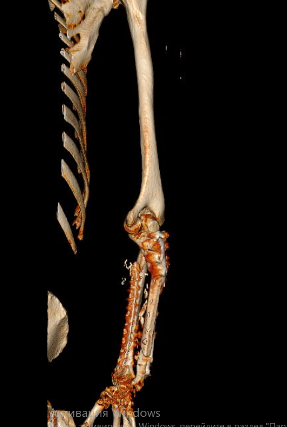

В связи с наличием рубцовой деформации и дефицита мягких тканей правого предплечья, дефекта правой локтевой кости до 10 см, было принято решение о проведении оперативного лечения в объеме пластики дефекта мягких тканей и локтевой кости свободным малоберцовым трансплантатом с фиксацией индивидуальной 3D-пластиной, металлоостеосинтеза лучевой кости правого предплечья пластиной. В рамках предоперационного планирования пациенту была выполнена компьютерная томография, на основе которой создан макет индивидуальной конструкции (рисунок 2).

На 95 сутки после ранения проведена реконструктивно-пластическая операция: пластика дефекта мягких тканей и локтевой кости правого предплечья свободным кожно-фасциально-костным малоберцовым лоскутом с фиксацией индивидуальной 3D пластиной, металлоостеосинтез лучевой кости правого предплечья пластиной.

На контрольных рентгенограммах КТ через 4 месяца после реконструктивно-пластической операции отмечается полная перестройка малоберцового трансплантата, замещенного дефекта.